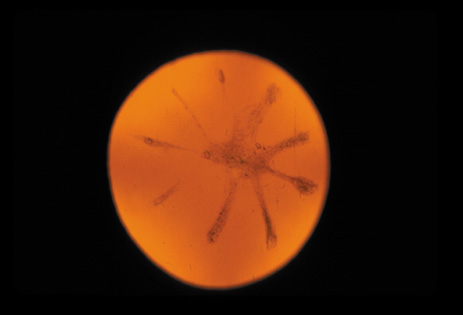

Cortical opacities have been clinically observed to develop earliest in the inferior half of the lens, especially the lower nasal quadrant.28 Epidemiologic29 and laboratory studies30 have suggested that cortical cataracts may be caused by ultraviolet rays from sunlight. The supraorbital margins may block the ultraviolet rays from falling over the upper part of the lens, thus making cortical cataract less frequent in the upper quadrants. Eventually these opacities also develop in the periphery in other quadrants, resulting in a circular array of spokes and peripheral cuneiform opacities (Fig. 9). Bands of central cortical fibers may become prominent and opacify centrally (Fig. 10). However, most cortical cataracts remain in the periphery for many years, even decades, before the central axis of the lens becomes involved, causing loss of vision late in the development of the cataract.

Fig. 9. Moderate cortical changes. Wedge-shaped (cuneiform) or spoke-like (wheel) peripheral changes are seen. These changes may be extensive but may not affect Snellen visual acuity since they occur in the periphery.